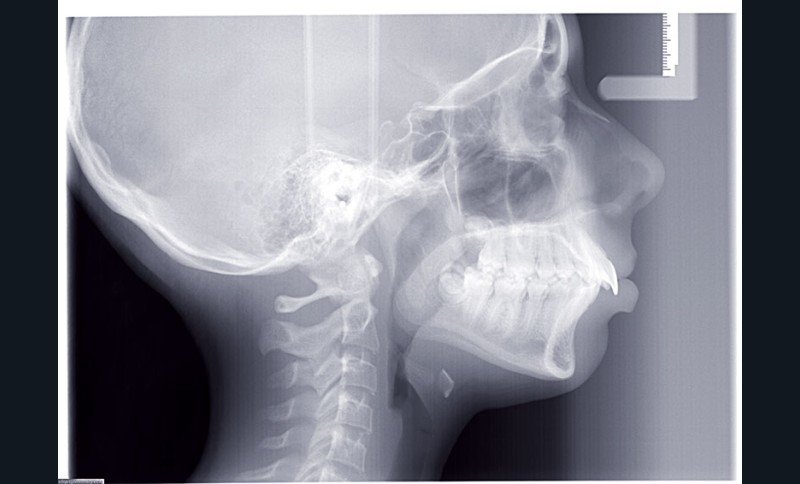

Elle présente une classe II squelettique par rétrognathie mandibulaire et une classe II dentaire molaire et canine droite et gauche associée à une biproalvéolie incisive maxillaire et mandibulaire.

L’environnement vertical est normodivergent.

Le contexte facial est délicat avec un profil cis-frontal, un angle naso-labial très ouvert et un sillon labio mentonnier marqué avec retour de la lèvre inférieure en arrière des incisives maxillaires.